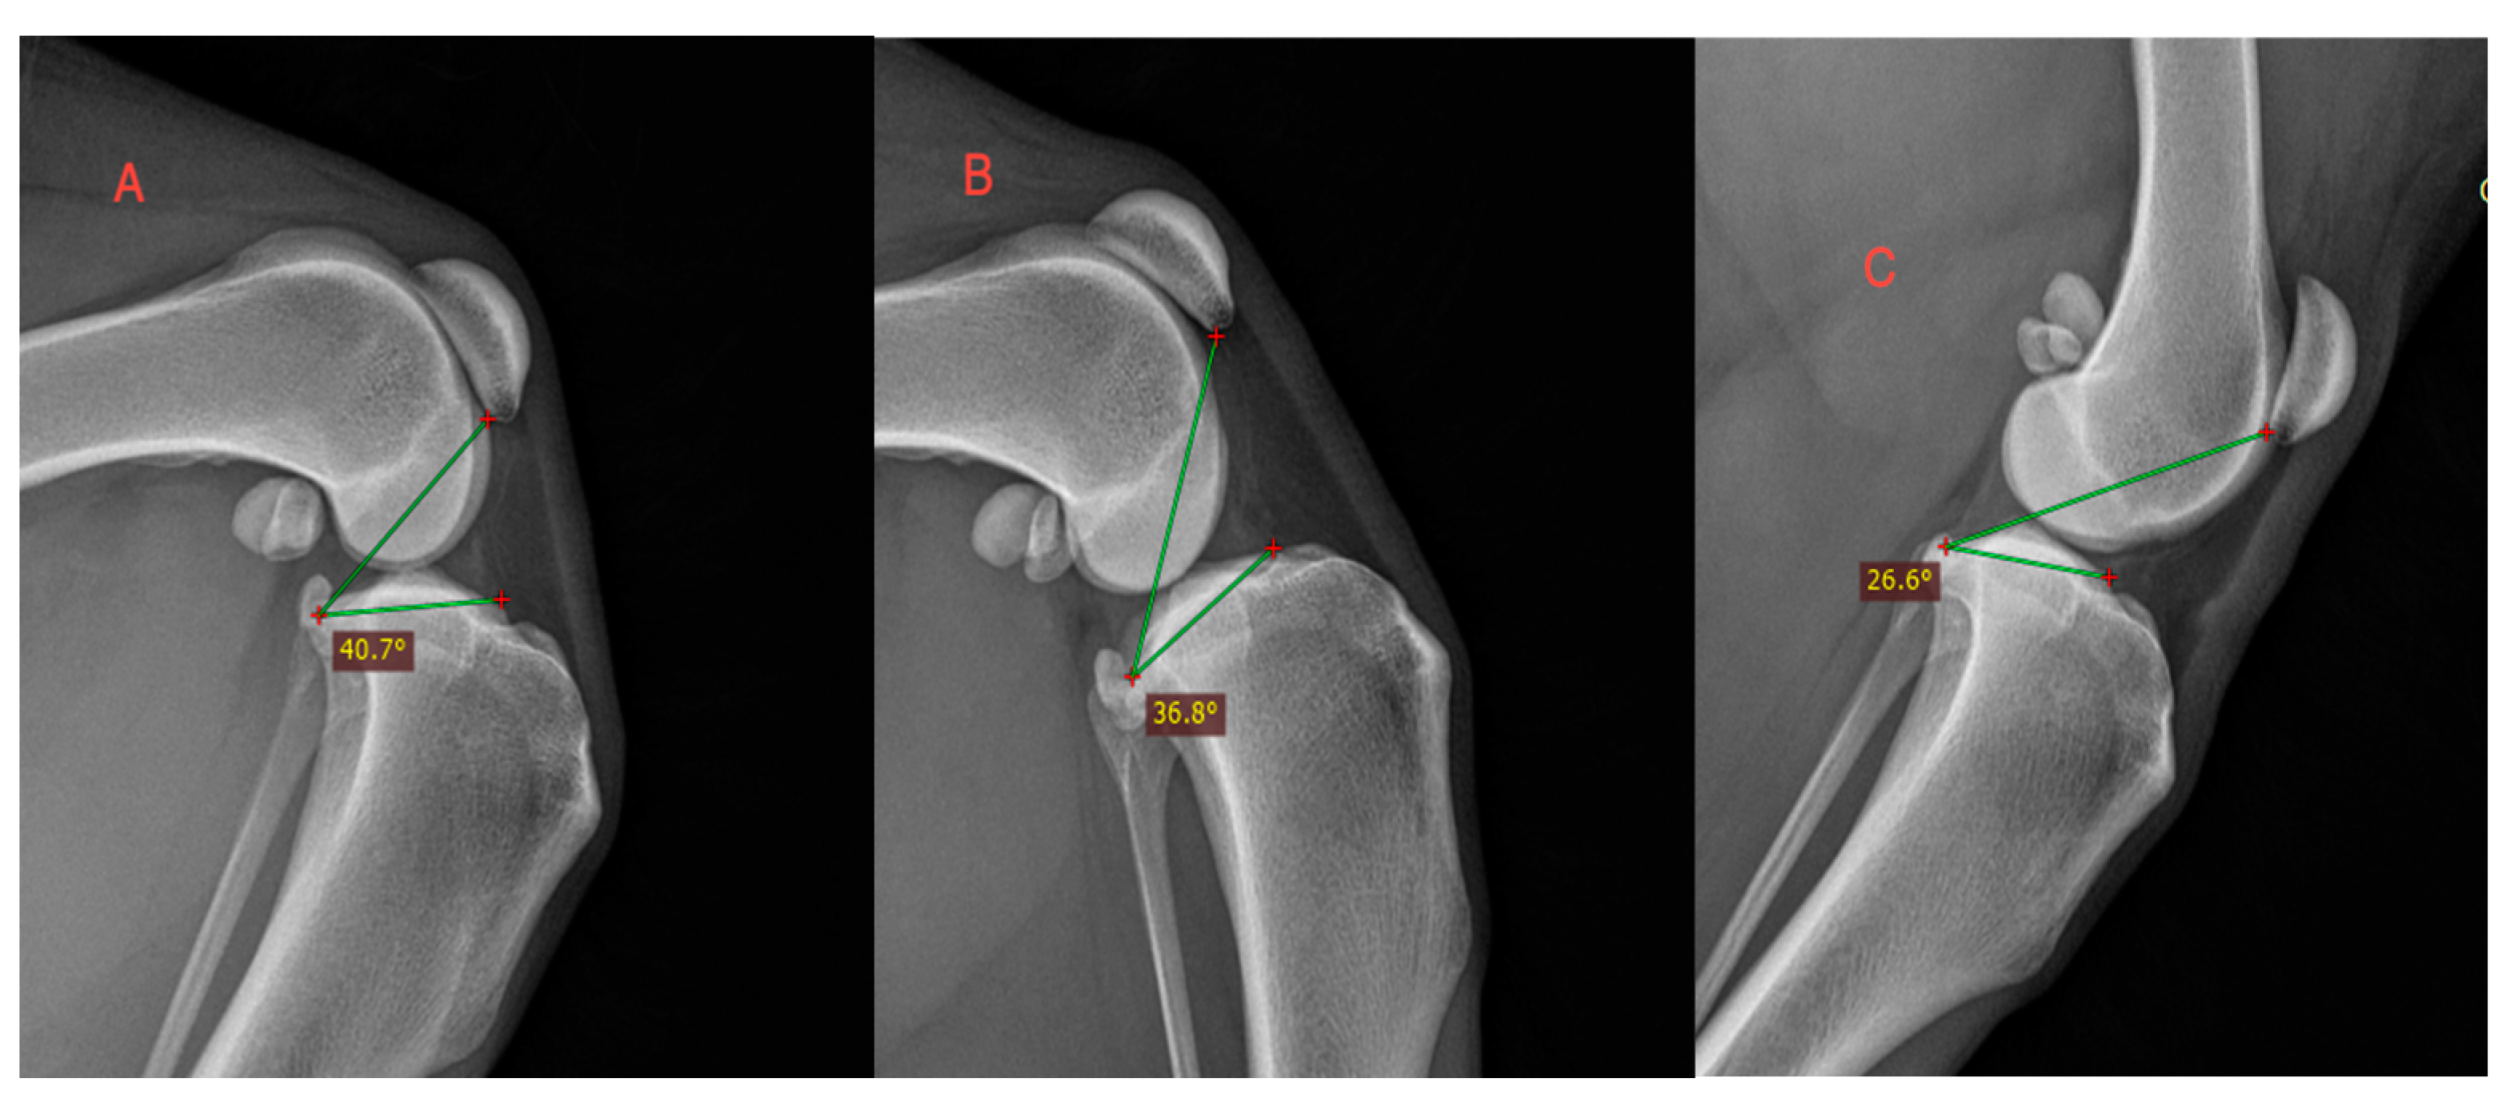

| Weight Group | Stifle Angle | Mean TPPA | ±SD 1 |

|---|---|---|---|

| ~45° | L | 43.67° | |

| M | 40.28° | ||

| S | 37.92° | ||

| Across groups 2 | 40.68° | ±4.28° | |

| ~90° | L | 35.12° | |

| M | 34.80° | ||

| S | 35.62° | ||

| Across groups | 35.26° | ±3.88° | |

| ~135° | L | 29.32° | |

| M | 26.37° | ||

| S | 28.06° | ||

| Across groups | 28.23° | ±3.54° |

| Observer | Mean TPPA | ±SD |

|---|---|---|

| 1 | 36.22° | ±4.52° |

| 2 | 37.10° | ±5.29° |

| 3 | 39.37° | ±4.66° |